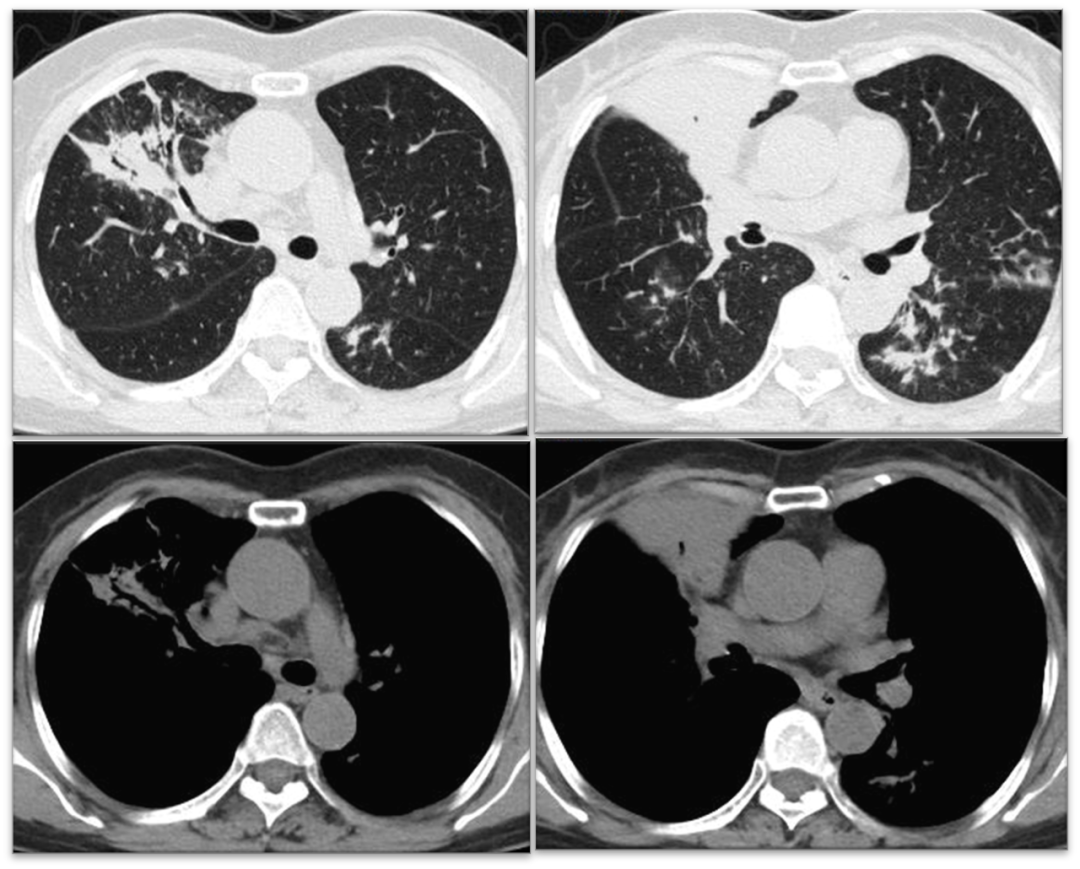

胸部CT平扫(2022年2月25日):右中肺叶、左肺舌叶及两肺下叶支气管扩张伴感染;两肺散在小结节;纵隔淋巴结稍大(图1)

图1   右中肺及左肺舌叶、两肺下叶支气管扩张伴感染